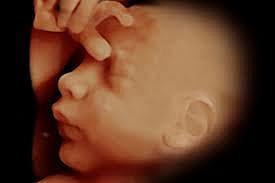

-The 3D

Since the late 80s and early 90s.